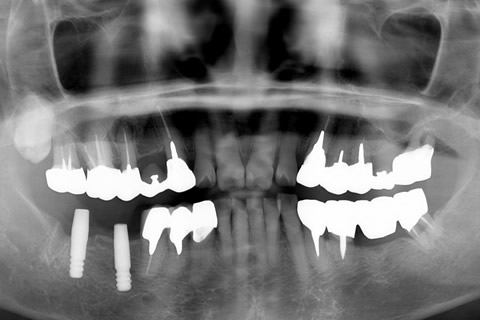

• 症例2

治療前

インプラント埋入時

治療後

年齢・性別

57歳男性

治療期間

3ヶ月

抜歯

なし

治療費

154万円

備考

左上5.6.7 及び左下6.7欠損

治療内容

左上5.6.7と左下6.7欠損部にインプラント埋入

施術の副作用(リスク)

オペによる知覚障害。インプラントによる歯肉炎。インプラント脱落。